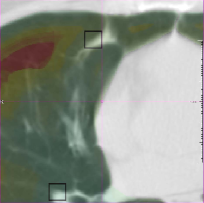

4.3 Qualitative validation

Muenzing et al. [2014] generated an uncertainty map by spatial interpolation of landmark-based quality estimates. On the contrary, our proposed system, which is trained on landmark locations, can be applied in all regions of the image. We showed this for two example images, see Fig. 5. It can be easily visualized that in the blue region, images are matched correctly. On the other hand, by tracking the vessels in the red region misalignment can be seen. Another note about the prediction is that there are no abrupt changes, and error varies smoothly from blue to yellow and then red, even though the error is predicted for each voxel independently.

Another example is given in Fig. 10(a-d). Although all landmarks indicate that the registration error is small in this slice, the quantitative results found several misregistered regions, which implies that few landmarks may not be sufficient to assess the registration quality of the whole image. In Fig. 10(e, f), it can be observed that the performance in the homogeneous area (left side of the images) is as good as the performance in the area with structure. The main reason of acceptable performance in the homogeneous area is that the training samples consist of landmarks as well as their neighborhood region, which can be homogeneous. Thus, the system is trained both for homogeneous regions and regions with structure.

Another example is given in Fig 10(g, h), where the proposed system is not able to predict the registration error correctly because of a shift in the slice direction.

Refer to caption

() Sample 1: IFsubscript𝐼𝐹{I}_{F}

(a) Sample 1: IM(𝐓b)subscript𝐼𝑀superscript𝐓b{I}_{M}(\bf{T^{\mathrm{b}}})

(b) Magnification of (a)

(c) Magnification of (b)

(d) Sample 2: IFsubscript𝐼𝐹{I}_{F}

(e) Sample 2: IM(𝐓b)subscript𝐼𝑀superscript𝐓b{I}_{M}(\bf{T^{\mathrm{b}}})

(f) Sample 3: IFsubscript𝐼𝐹{I}_{F}

(g) Sample 3: IM(𝐓b)subscript𝐼𝑀superscript𝐓b{I}_{M}(\bf{T^{\mathrm{b}}})

Figure 10: Several samples from the SPREAD dataset. The left column shows the fixed image with the ground truth registration error overlaid in color. The right column shows the moving image after registration with the registration error predicted by the proposed method overlaid in color.